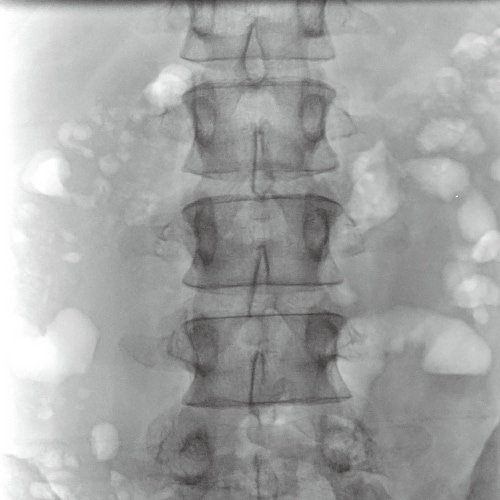

Lumber spine examination